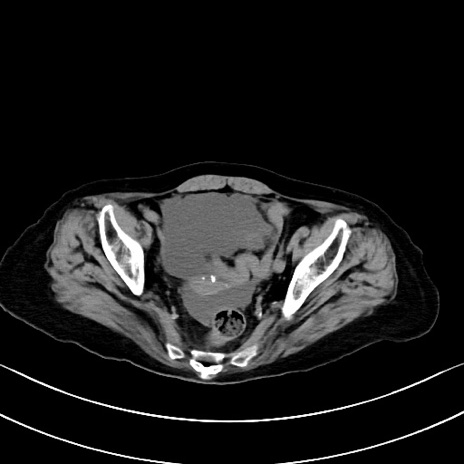

症例40(横断像)他院1日前

横断像

他院CT